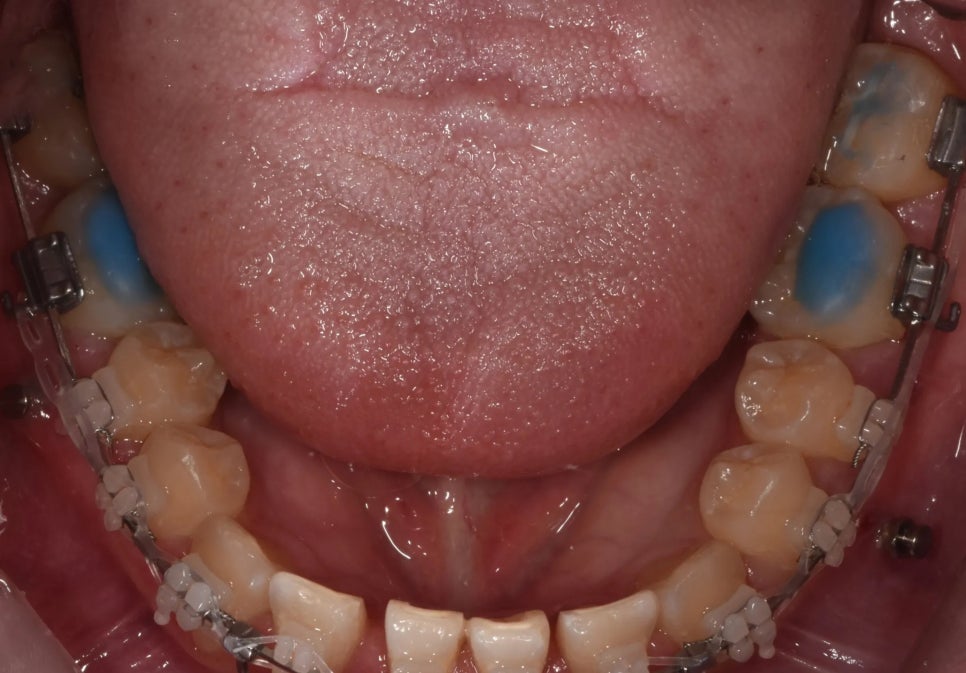

치료 2단계 – 미니스크류를 이용한 아랫니 후방 견인

위턱 쪽 작업이 진행되어 가면서, 아래턱에도 본격적인 치료를 시작했습니다. 아래턱에 미니스크류(아주 작은 나사 형태의 고정장치)를 심어서, 돌출된 아래 치열 전체를 뒤쪽으로 끌어당기는 방법을 사용했어요.

미니스크류는 뼈에 직접 고정되기 때문에 움직이지 않는 절대적인 기준점 역할을 합니다. 이 고정점을 이용해 스프링이나 체인으로 지속적인 힘을 가하면, 아래 치열이 조금씩 뒤로 이동하게 됩니다.

미니스크류를 활용하여 아래 치열을 뒤쪽으로 이동시키는 과정

정리하면, 위쪽 앞니는 앞으로, 아래쪽 치열은 뒤로 이동시키는 이중 효과로 반대교합을 교정하는 전략이에요. 이렇게 양쪽에서 동시에 접근하면 한쪽만 움직이는 것보다 훨씬 많이 위아랫니의 관계를 개선해줄 수 있습니다.

아래 치열 전체를 뒤로 보내는 중입니다

교정 전 저희가 수많은 증례사진을 보여드렸음에도 불구하고, 환자분은 처음 윗니 확장할 때 까지만 해도 '이게 진짜 되는 것 맞나...'하고 반신반의 하셨습니다. 앞니 넘겨드리고 어금니에 있던 파란 바이트레진 떼는 날 가장 기뻐하셨는데, 그 순간이 잊혀지지 않네요. 얼굴은 그 날 이미 거의 완성되었습니다.